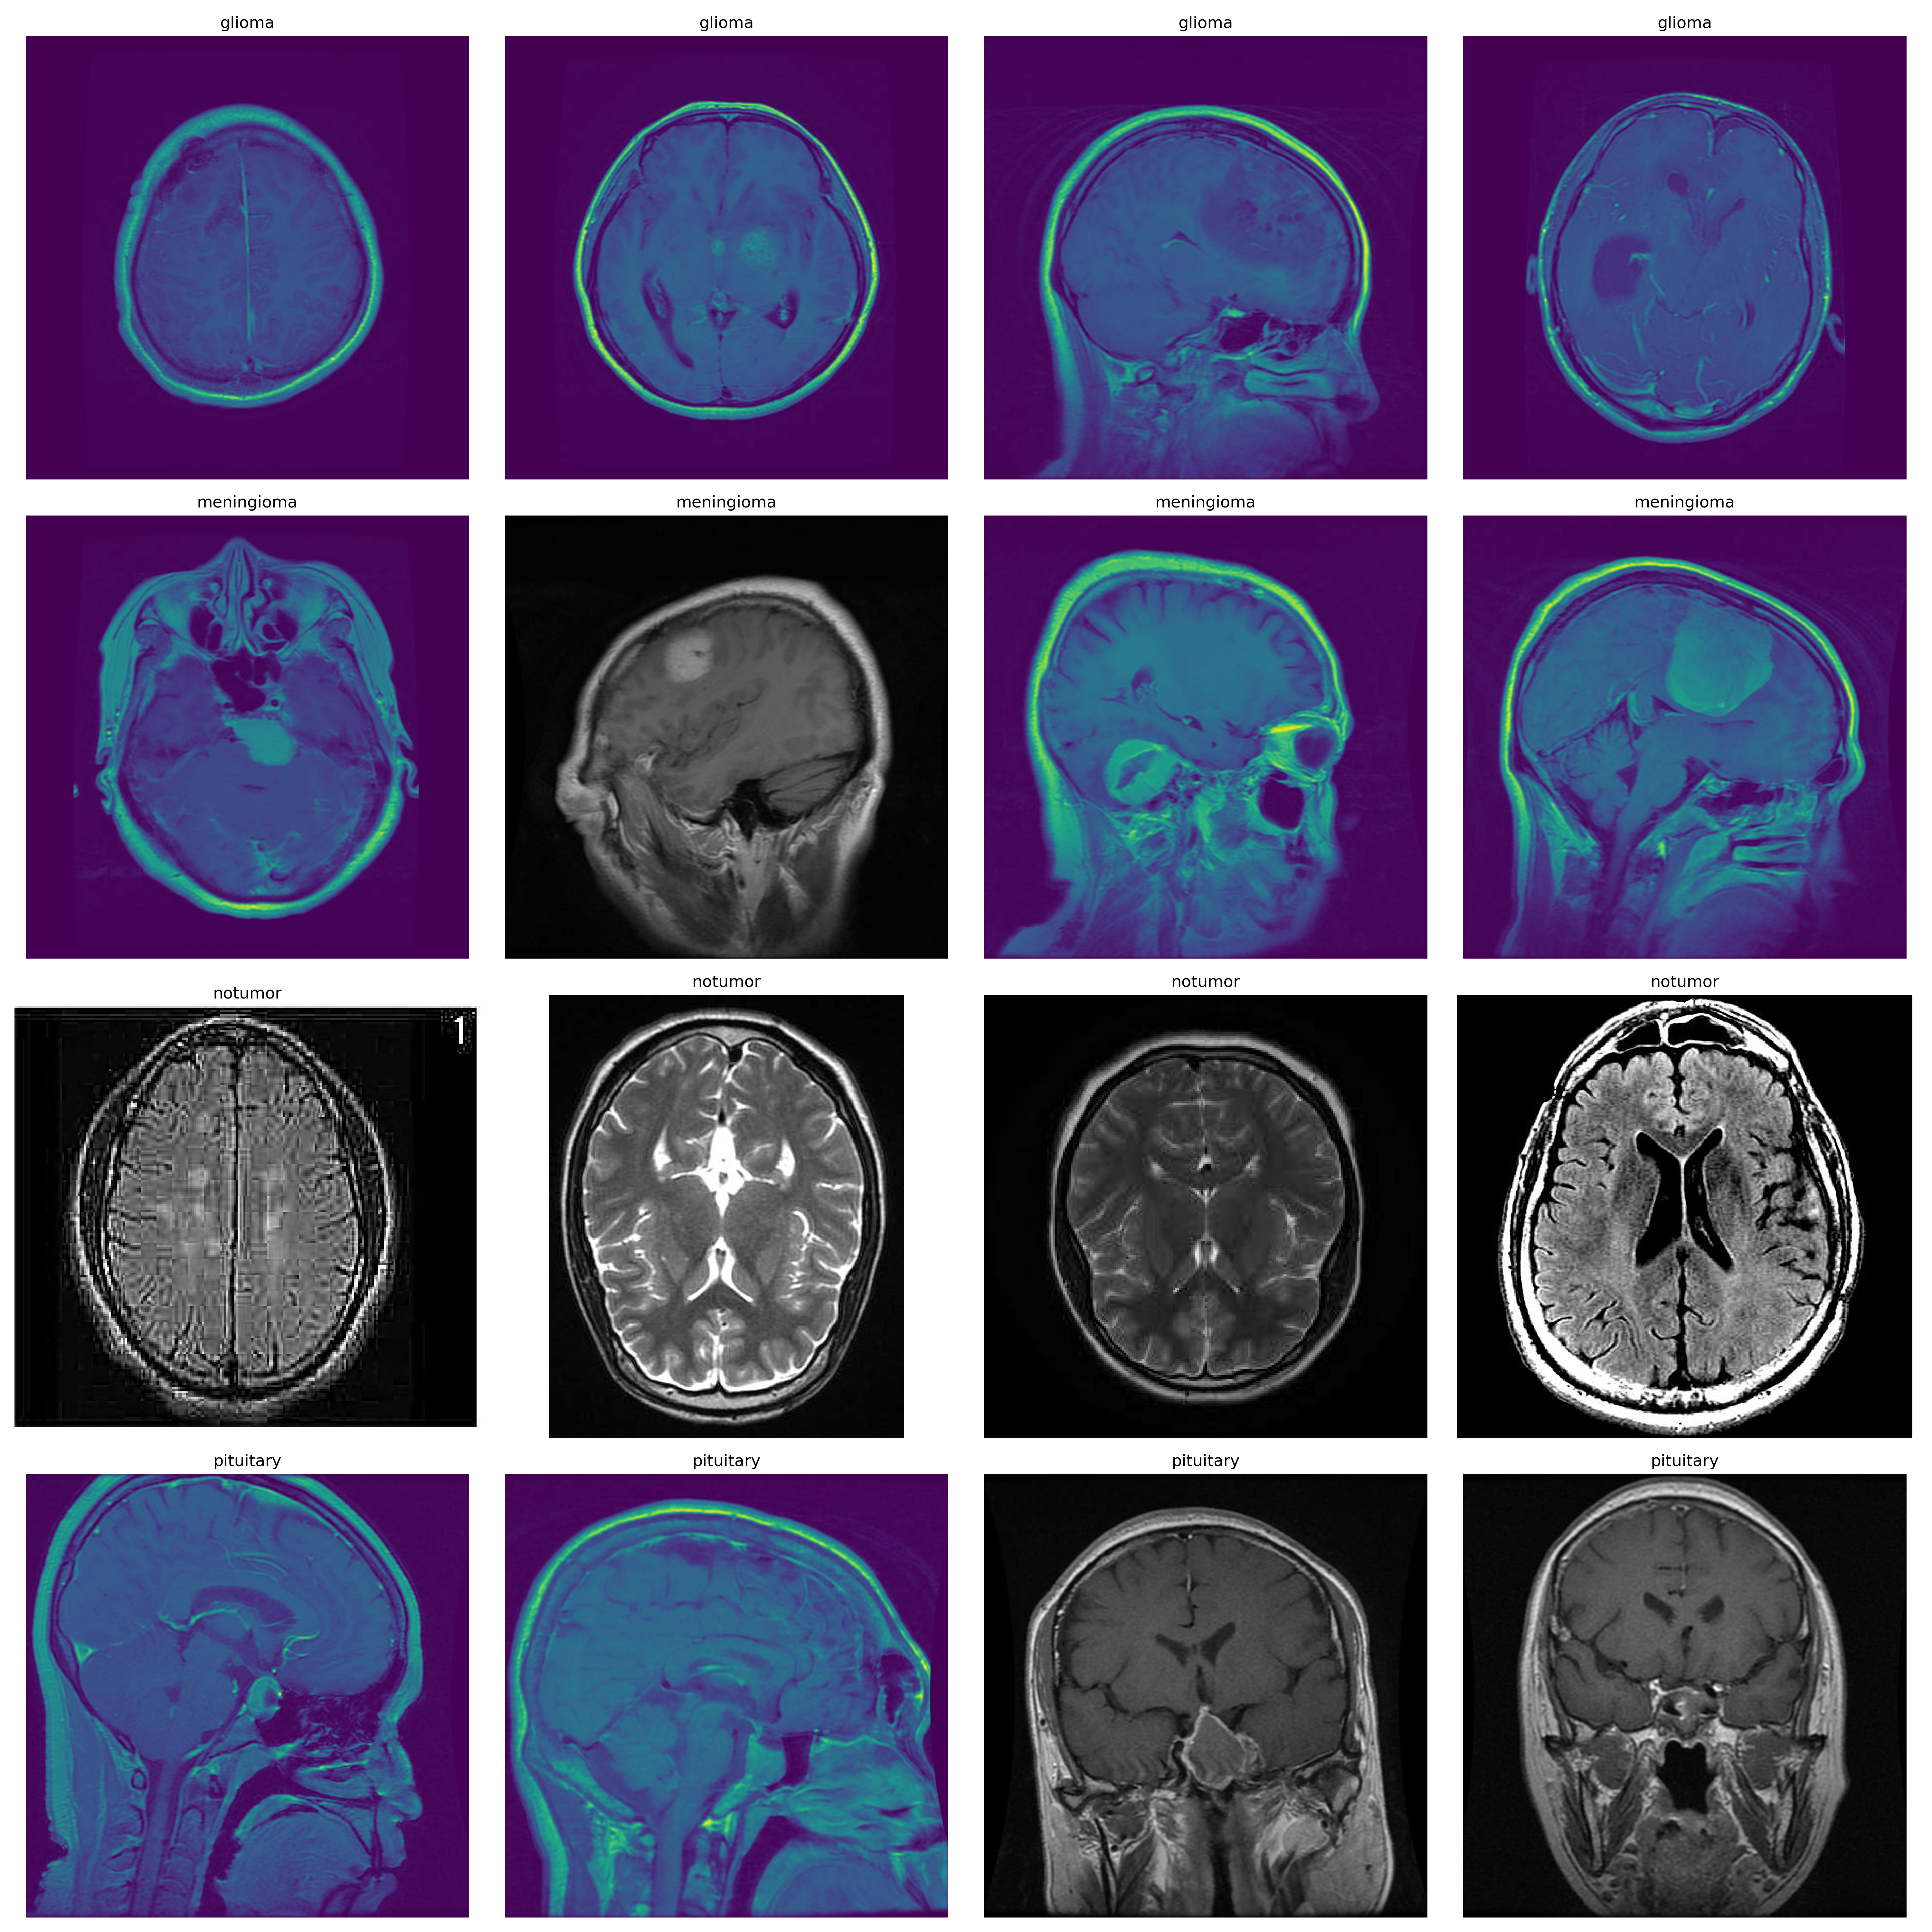

This study utilized a composite dataset from three sources: Figshare, SARTAJ, and Br35H [15]. This resulted in a total of 7,023 MRI images of the human brain, classified into four categories: glioma, meningioma, no tumor, and pituitary. Due to potential mislabeling in the SARTAJ dataset, the glioma images from this source were replaced with more accurate samples from Figshare. The training set comprises 5,712 pictures distributed across the four classes, while the test set includes 1,311 images. Each class is well-represented, ensuring robust model training and evaluation. The data preprocessing involved loading the images, normalizing pixel values, and applying data augmentation techniques to enhance the model’s generalization capabilities. This meticulous data preparation process contributes to the model’s reliability in classifying brain tumors accurately. The dataset used in this study is visualized in Figure 1, showcasing representative samples from each class.

Refer to caption

Figure 1: Sample images from the brain tumor MRI dataset across four classes: glioma, meningioma, no tumor, and pituitary.